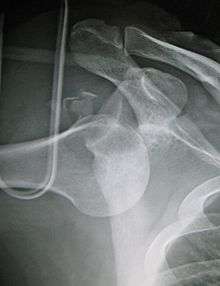

An inferior dislocation of the shoulder after an automobile accident. Note how the humerus is abducted. Also present is a fracture of the greater tuberosity.

Inferior dislocation is the least likely, occurring in less than 1%. This condition is also called luxatio erecta because the arm appears to be permanently held upward or behind the head.[8] It is caused by a hyper abduction of the arm that forces the humeral head against the acromion. Such injuries have a high complication rate as many vascular, neurological, tendon, and ligament injuries are likely to occur from this mechanism of injury.